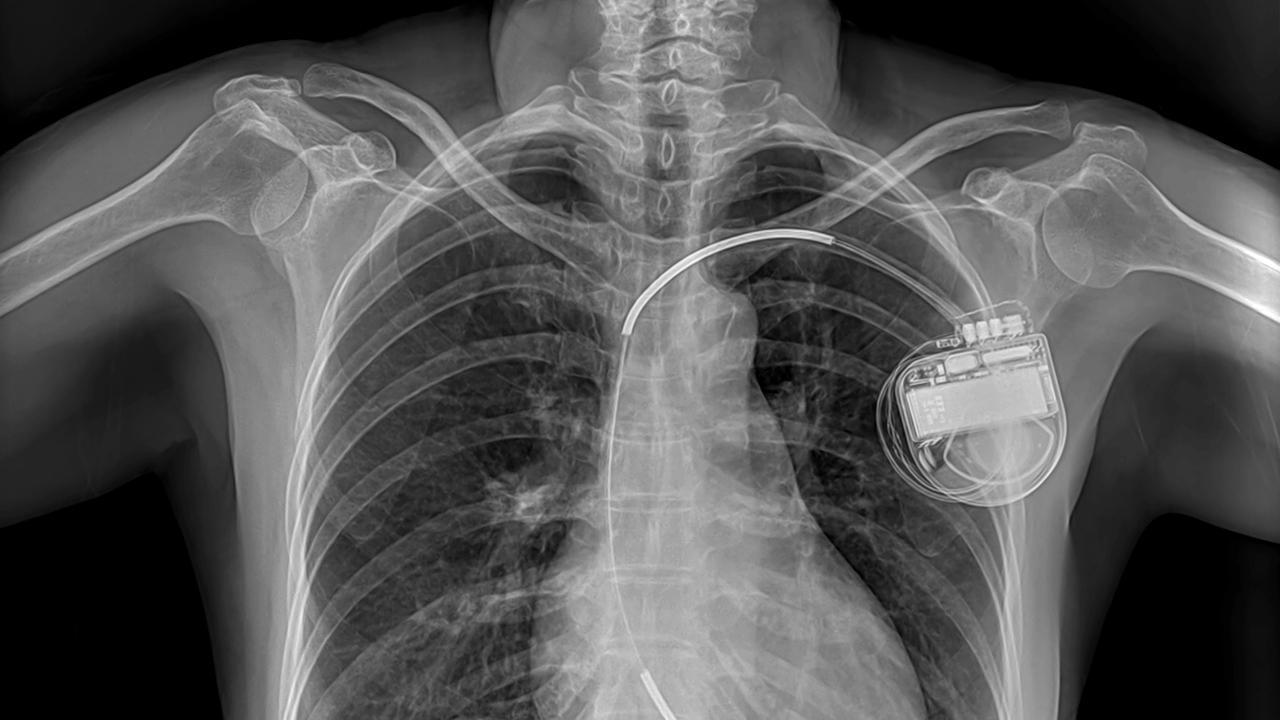

Пациентом была женщина пятидесяти семи лет, у которой восемью годами ранее случился сердечный приступ. С тех пор у нее регулярно были приступы аритмии, а однажды ей удалось выжить лишь потому, что она упала в обморок на пороге больницы, где ее спасли с помощью дефибриллятора. Мировски наблюдал, как хирург Леви Уоткинс прикрепляет к ее сердцу электроды. Один из них был пропущен через вену в правое предсердие, а другой электрод в виде квадратной пластины был закреплен поверх околосердечной сумки. Само устройство было размещено в кармане под кожей живота, а затем подсоединено проводами к обоим электродам. Эта первая операция прошла невероятно успешно: когда пять месяцев спустя Мировски сделал о ней доклад, пациентка была жива и больше не страдала от фибрилляции желудочков.

К 2009 году по всему миру ежегодно имплантировалось уже более 250 000 ИКД. Современные модели гораздо более совершеннее тех, что были в 1980-х. Они способы охватить более широкий спектр и вылечить от различных видов аритмии и как правило сочетают в одном устройстве функционал и ИКД, и кардиостимулятора. Сами электрокардиостимуляторы тоже преобразились до неузнаваемости: теперь они полностью программируемые и подстраиваются под потребности пациента, а также ведут регистрацию сердечной деятельности для ее дальнейшего анализа — данные передаются на компьютер по беспроводной связи или через Интернет.